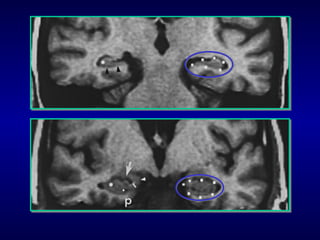

NEUROIMAGEM

Inicia com atrofia hipocampal e do córtex

entorrinal.

Associada ao genótipo ApoE4 em idosos.

Associada com a presenilina 1 e 2 nos

adultos jovens.